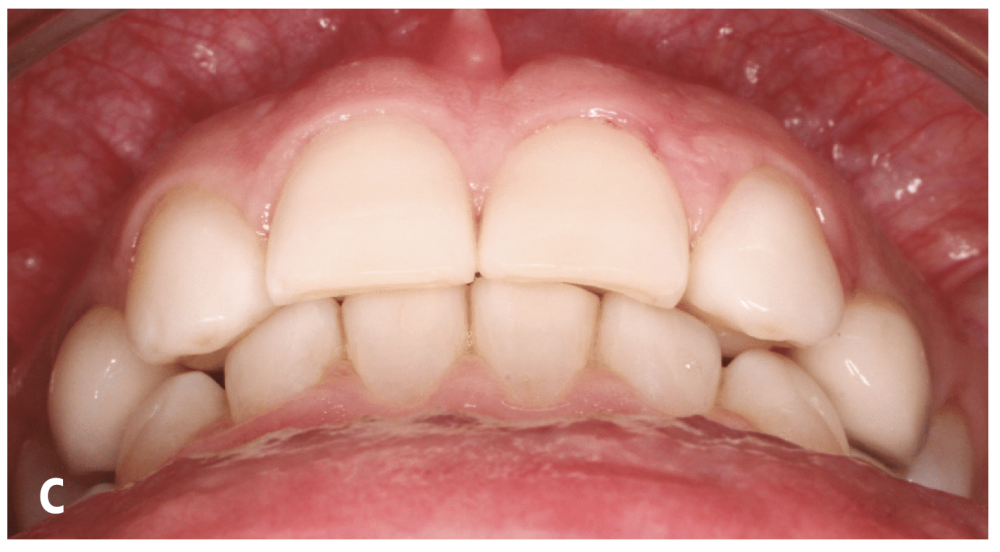

1. Limites sociales : la conférencière s’est appuyée l’exemple d’un patient de 30 ans présentant des agénésies des latérales avec des espaces en mésial et distal des canines, très inesthétiques, à l’origine de la consultation. Le repositionnement des canines et le remplacement des latérales par des implants ont nécessité trois ans et quarante-deux rendez-vous au cabinet. Ce choix de plan de traitement est acceptable pour un adolescent, mais pas pour un trentenaire. Dans ce cas, l’option la plus appropriée aurait été de rapprocher les canines contre les incisives centrales. La suite du traitement consiste à maquiller…